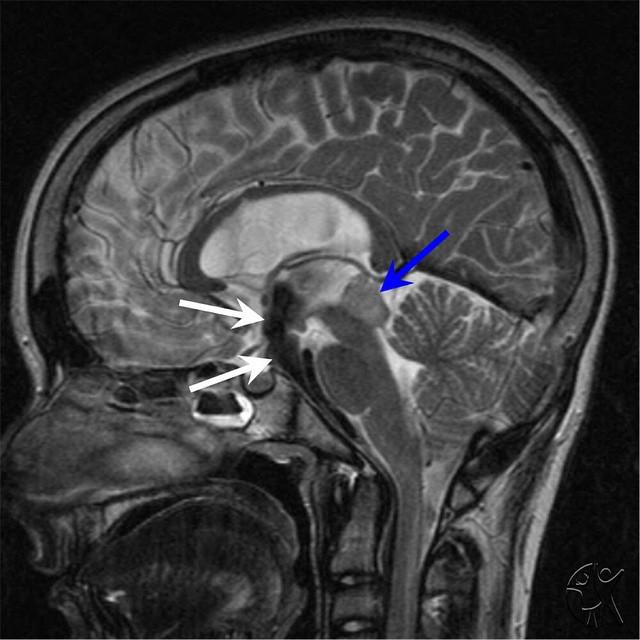

КТ-изображения липомы мозолистого тела